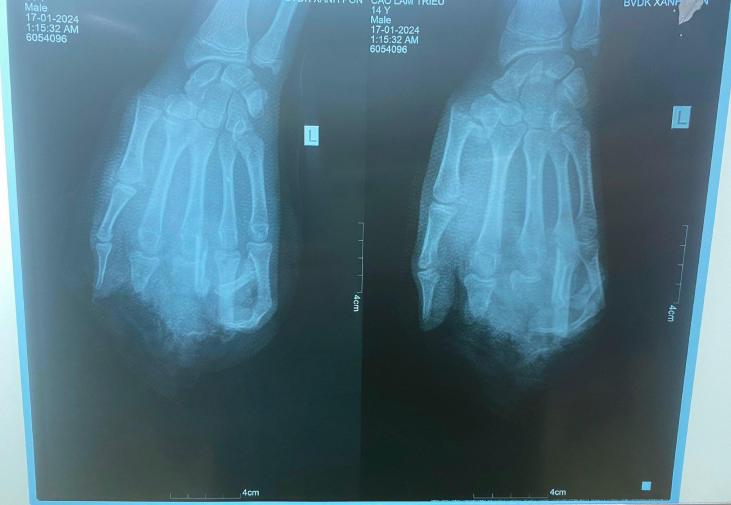

Bệnh nhận C.T.L., 14 tuổi, ngụ Hải Dương, được gia đình đưa vào Bệnh viện Đa khoa Xanh Pôn (Hà Nội) cấp cứu trong tình trạng tình trạng dập nát bàn tay trái, gãy xương bàn ngón I, đầu ngón I, V còn hồng.

Hình ảnh phim chụp X-quang của bệnh nhân. Ảnh: BVCC.

Với tổn thương này, bác sĩ đánh giá vấn đề chức năng bàn tay của bệnh nhân sẽ bị giảm đi rất nhiều, ảnh hưởng lớn đến học tập, sinh hoạt và lao động sau này, đặc biệt còn ảnh hưởng đến tâm lý.